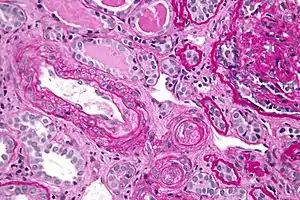

In the kidneys, chronic hypertension has a great impact on the kidney vasculature, leading to pathologic changes in the small arteries of the kidney. Affected arteries develop endothelial dysfunction and impairment of normal vasodilation, which alter kidney autoregulation. When the kidneys' autoregulatory system is disrupted, the intraglomerular pressure starts to vary directly with the systemic arterial pressure, thus offering no protection to the kidney during blood pressure fluctuations. The renin-aldosterone-angiotensin system can be activated, leading to further vasoconstriction and damage. During a hypertensive crisis, this can lead to acute kidney ischemia, with hypoperfusion, involvement of other organs, and subsequent dysfunction. After an acute event, this endothelial dysfunction has persisted for years.[9]